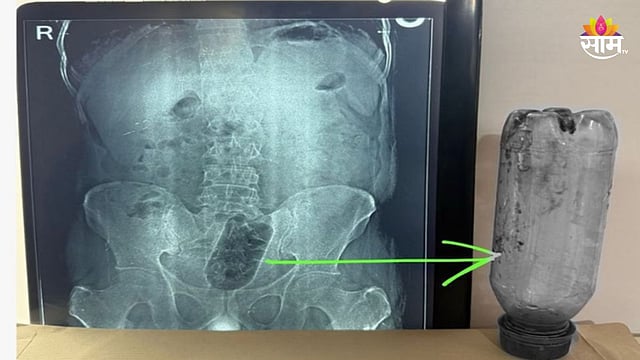

मिळालेल्या माहितीनुसार, उत्तर प्रदेशातील आग्रा येथील साकेत कॉलनी येथील नवदीप रुग्णालयात शस्त्रक्रियेद्वारे एका तरुणाच्या गुदाशयातून एक लिटरची प्लास्टिकची बाटली काढण्यात आली. मंगळवारी हा ३८ वर्षांचा तरुण तरुणालयात दाखल झाला होता. ज्यावेळी एक्सरे काढण्यात आले तेव्हा त्याच्या मलाशयामध्ये १ लीटरची पाण्याची बाटली अडकल्याचे दिसून आले. यामुळे तरुणाला प्रचंड वेदना होत होत्या.

शस्त्रक्रिया करणारे डॉ. सुनील शर्मा यांनी सांगितले की, तरुणाने गुदद्वारातून एक लिटर पाण्याची बाटली आत घातली. ही बाटली त्याच्या गुदाशयात अडकली. त्याला असह्य वेदना होत होत्या आणि त्याची प्रकृती गंभीर झाल्यावर त्याला तातडीने रुग्णालयात दाखल करण्यात आले. बाटली ३६ तासांपासून त्याच्या गुदायशयात अडकली होती. एक्स-रे नंतर एका विशेष टीमने सुमारे सव्वा तासांच्या शस्त्रक्रियेनंतर बाटली बाहेर काढली. जखम बरी झाल्यानंतर आणि आतड्यांसंबंधी कोणतीही समस्या न आल्यानंतर रुग्णाला घरी सोडण्यात आले.